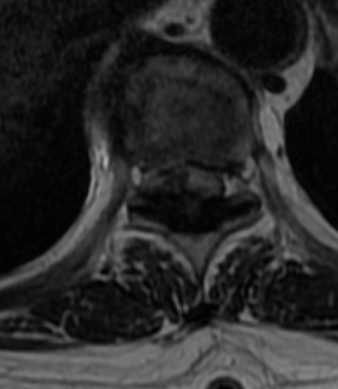

患者1+年前无明显诱因出现行走不稳症状,自诉有“踩棉感”,继而出行行走困难,近1+月明显加重,无法上下楼。对于一个居住在5楼(步梯)的患者来说,出门也变成了奢望。患者曾因为此症状反复就诊于省内外多家三甲医院,因体征不典型及相对复杂的既往史,曾被考虑为“糖尿病周围神经病变”、“焦虑症”等,长达1+年的治疗并没有使症状得到改善,反而逐渐加重,行走都只能靠助行器,甚至弯腰拾物简单的动作都不能执行,抱着尝试再一下的心态,患者就诊于我院,以椎管狭窄收入病房。入院早期因患者既往“焦虑症”的诊断,以及症状体征的不典型也给我科医务工作者在考虑诊断时造成了误导,经过反复积极查体考虑椎管狭窄,于是积极完善了脊柱的影像学检查,颈椎间盘、胸部及腰椎间盘CT:1、颈椎退行性变并颈椎椎管明显狭窄、颈2-3左侧椎间孔变窄;2、胸椎退行性变并胸1-7节段椎管轻度狭窄。胸腰椎MRI回示:1、颈椎退行性变并颈1-7水平后纵韧带增厚、钙化,继发椎管节段性狭窄。2、胸椎多段黄韧带增厚、钙化,继发相应椎管狭窄,脊髓节段变性(胸1-2及胸9-10水平)。结果出来后医生犯难了,问题找到的同时发现狭窄的地方及位置太多了,对于这种颈胸椎多处狭窄的病人想通过一个手术去解决几乎是不可能事情,针对此种情况,科内医师多次病例讨论,结合患者影像学检查、症状及体征,瞄准了T9-10平面的巨大黄韧带骨化。

此处黄韧带骨化严重,脊髓压迫严重,椎管狭窄处约只有4mm。考虑到手术难度较大,传统麻醉下手术瘫痪风险甚至可达20%以上,2022年6月24日科室内部邀请医务部参与最终讨论,报请重大手术,并决定使用局部麻醉与全凭静脉麻醉联合,保持术中唤醒随时检查下肢运动功能的麻醉方式,利用椎间孔镜可以直视的优点,行椎间孔镜下胸椎后路T9-T10椎板切除减压、黄韧带摘除、脊神经探查松解术。在2022年6月25日经过长达4小时20分钟的精细操作下最终将患者的压迫解除。几乎完整取出了巨大的骨化黄韧带。

术后积极控制血糖、血压,预防并发症,术后复查见: